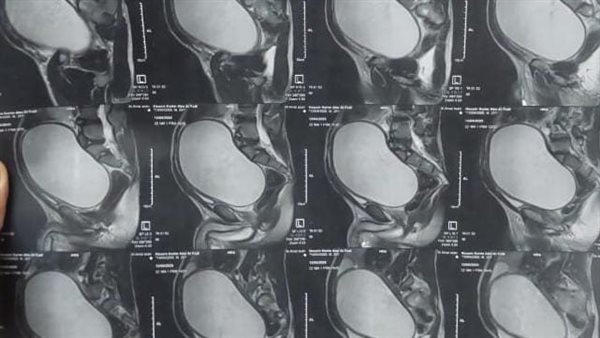

فريق طبي بأسيوط يجري جراحة معقدة لشاب يعاني من كيس نادر بين المثانة والمستقيم